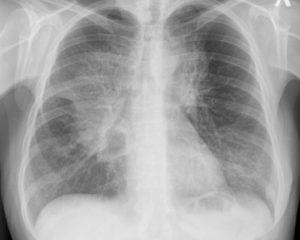

Рентген легких позволяет получить черно-белое изображение органов грудной клетки, с помощью которого специалист имеет возможность увидеть патологические изменения и подобрать подходящее лечение.

Рентгенография легких получила широкое распространение за счет высокой информативности и низкой стоимости метода. Исследование незаменимо в терапевтической, пульмонологической, фтизиатрической, онкологической практике и в области торакальной хирургии.

Рентген легких значительно упрощает выявление пневмоний и плевритов различного происхождения, злокачественных образований на ранней стадии развития, метастазирования в легкие и бронхи, а также пневмотораксов, туберкулеза, признаков системных заболеваний (волчанки, саркоидоза и других) и профессиональных изменений органов дыхания (антракоз, силикоз).